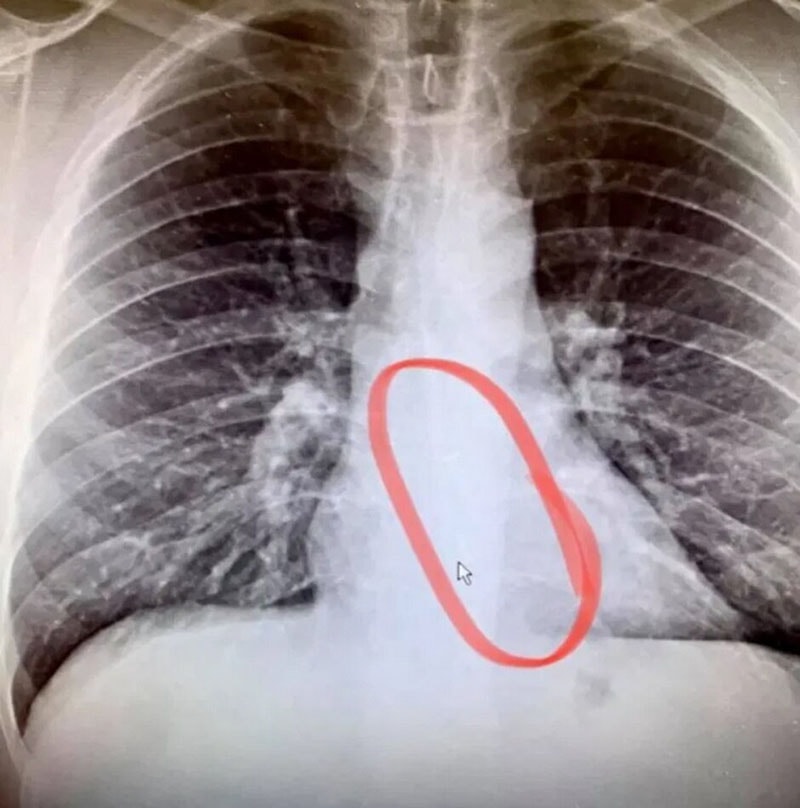

بنابراین او سریعا به اتاق اورژانس رفت و نتیجه آزمایش اشعه ایکس، نشان داد که ایرپاد گم شده در مری او گیر کرده است. با آندوسکوپی اضطراری، ایرپاد یاد شده بدون هیچ گونه درد و خونریزی، از محل خارج شد. وی اعتراف کرد که در این مورد بسیار خوش شانس بوده و در ادامه چنین اظهار داشت: